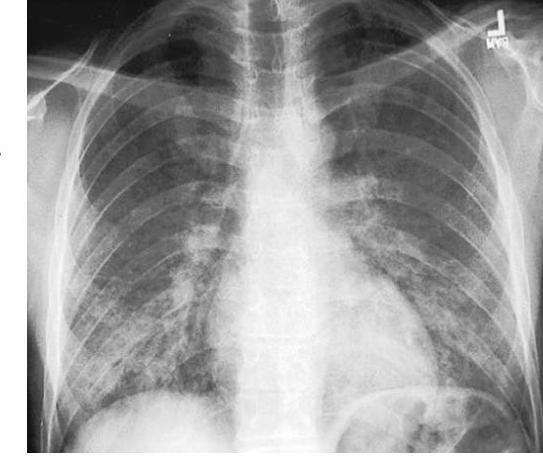

# Pneumocystis jirovecii ## DEFINICIÓN Pneumocystis jirovecii es una causa común de neumonía en pacientes inmunodeprimidos, sobre todo en las personas infectadas por **HIV** y en las que recibieron corticoides sistémicos. Los síntomas incluyen fiebre, disnea y tos seca. El diagnóstico requiere la demostración del microorganismo en una muestra de esputo inducido o muestra por broncoscopia. El tratamiento es con antibióticos, en general trimetoprim/sulfametoxazol o dapsona/trimetoprim, clindamicina/primaquina, atovacuona o pentamidina. Los pacientes con PaO2 < 70 mm Hg reciben corticoesteroides sistémicos. En general, el pronóstico es bueno con el tratamiento oportuno. ## ETIOLOGÍA P. jirovecii es un **HONGO OPORTUNISTA** ubicuo transmitido por aerosoles y no provoca enfermedad alguna en pacientes inmunocompetentes. Riesgo de desarrollar neumonía por P. jirovecii: - Pacientes con infección por HIV y recuentos de linfocitos T CD4+ < 200/\µL - Receptores de trasplante de órganos - Pacientes con cánceres hematológicos - Pacientes que toman corticosteroides ## PROFILAXIS ## INDICACIONES - Linfocitos CD4 <200 células/mm3 - Linfocitos CD4 <14% - Historia de candidiasis orofaríngea - Historia de enfermedades definitorias de SIDA ## 1ra elección: Trimetoprim con Sulfametoxazol (TMP/SMX). Dosis recomendada: 800/160 mg (dosis doble) una vez al día, que además confiere profilaxis contra toxoplasmosis, también útil si se usa 3 veces por semana, (BI) o 400/80, tabletas simples, una vez al día. Los pacientes que reciben sulfadiazina-pirimetamina como tratamiento o profilaxis para toxoplasmosis no requieren tratamiento adicional con TMP/SMZ. Suspender cuando la cuenta de CD4 sea >200 células/mm3 por al menos 3 meses en respuesta al tratamiento **ARV**. # CLÍNICA - Fiebre - Disnea (frecuente) - Tos seca, no productiva El cuadro evoluciona durante varias semanas (si es por VIH) o durante varios días (por otras causas de alteraciones de la inmunidad mediada por células). ## DIAGNÓSTICO ## RADIOGRAFÍA DE TÓRAX Muestra de modo característico infiltrados bilaterales perihiliares y difusos, pero del 20 al 30% de los pacientes tienen radiografías normales. Muestra características opacidades granulares bilaterales generalizadas. ## VISUALIZACIÓN MICROORGANISMO  ## TINCIÓN DE AZUL DE TOLUIDINA ## TINCIÓN DE PLATA METENAMINA DE GOMORI ## TRATAMIENTO (1ra elección) ## 1ra elección: Trimetoprim/sulfametoxazol (TMP/SMX) - 4 a 5 mg/kg IV o VO 3 veces al día durante 14 a 21 días - Efecto secundario **Grave**: **TOXICIDAD DE MÉDULA ÓSEA** ## ALTERNATIVAS: - Pentamidina 4 mg/kg IV una vez al día - Atovacuona 750 mg VO dos veces al día - Trimetoprima 5 mg/kg VO cuatro veces al día con dapsona 100 mg VO una vez al día - Clindamicina 300 a 900 mg IV cada 6 a 8 h con primaquina base de 15 a 30 mg/día VO